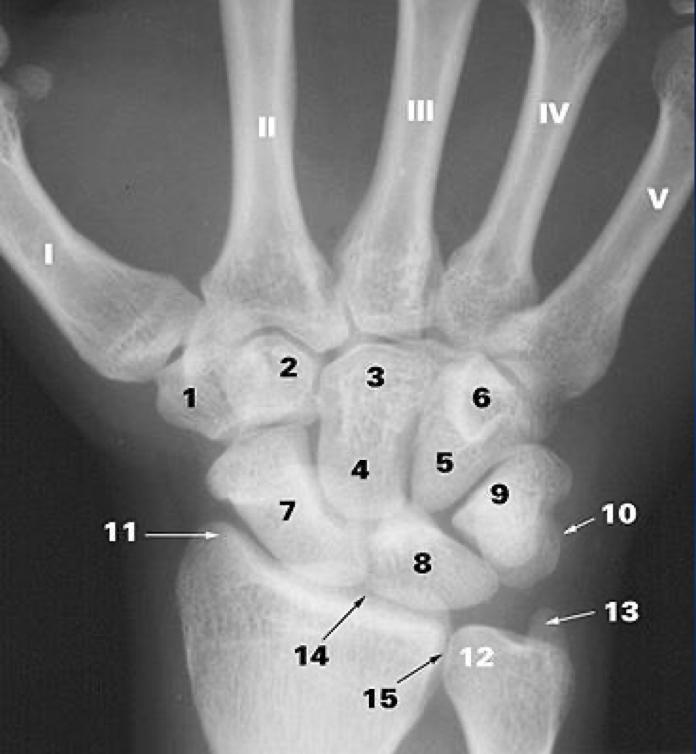

1

What is 1?

trapezium b.

2

What is 2?

trapezoid b.

3

What is 3?

capitate b.

4

What is 5?

5

What is 6?

6

What is 7?

scaphoid b.

7

What is 8?

lunate b.

8

What is 9?

triquetrum b.

9

What is 10?

pisiform

10

What is 11?

styloid process of the radius

11

What is 12?

head of the ulna

12

What is 13?

styloid process of ulna